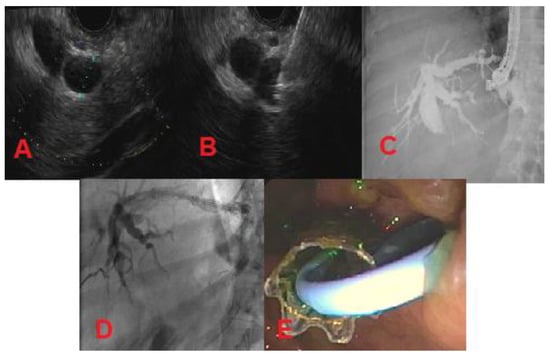

4. Endoscopic Ultrasound-Guided Biliary Drainage